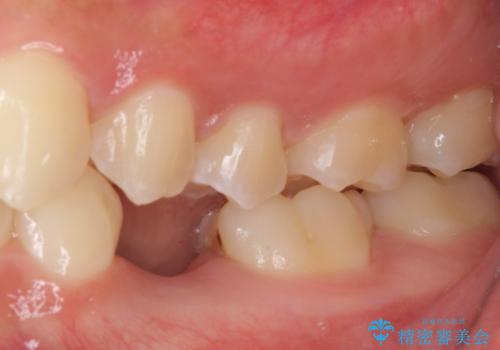

- 前歯の叢生と、奥歯の咬み合わせの悪さを気にして来院された患者様です。

左下には後続永久歯の欠損した乳歯が残存しており、叢生を相まって咬合関係が乱れていました。

乳歯は抜歯し、インビザラインにて矯正治療を行いながら、並行してインプラントによる補綴治療を行うこととしました。